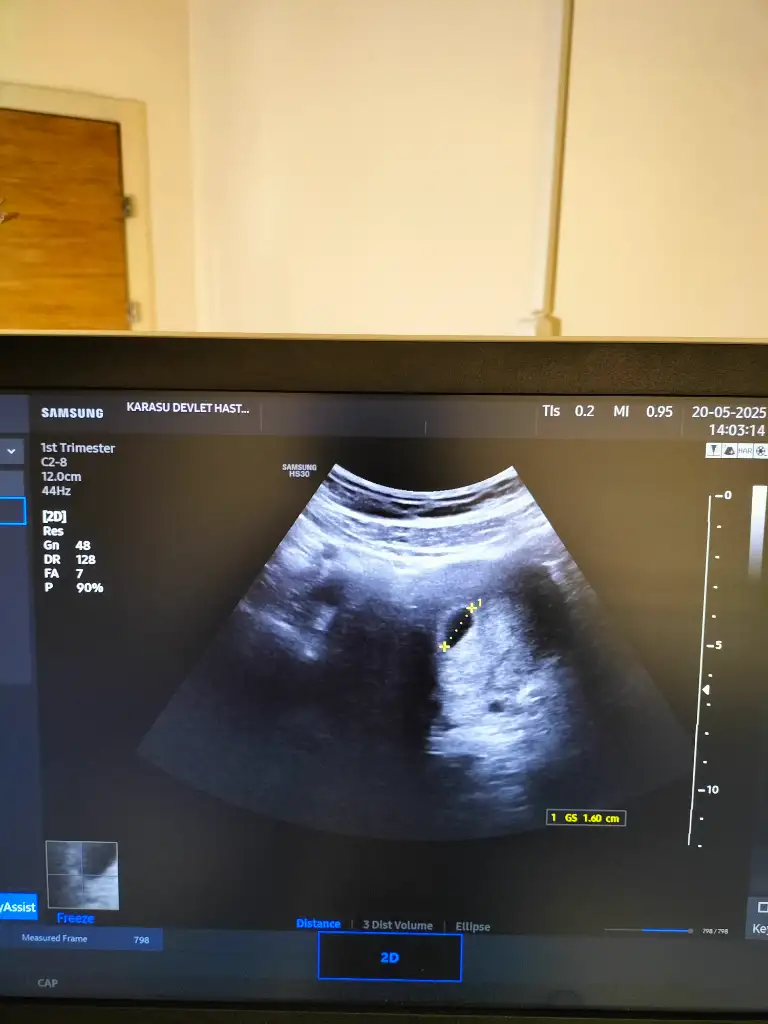

.Kızçelerim günaydınsalı günü doktora gittiğimde her şey yolunda yolk sac var kalp atışı için bayram sonrasını bekleyelim dedi testler istedi şeker vs. Ultrason görüntüm nasıl bı bakabilir misiniz? Geçende paylaştım ama fazla gören olmamıştı

Kesenin şekli boyutu normale benziyor canımKızlar benim ultrason resmimide bakarmisiniz? Doktorum yolk sac var bir sıkıntı yok kalp atışı için bayramdan sonraya gel dedi. Tecrübeli anneler sizde bı bakarmisiniz